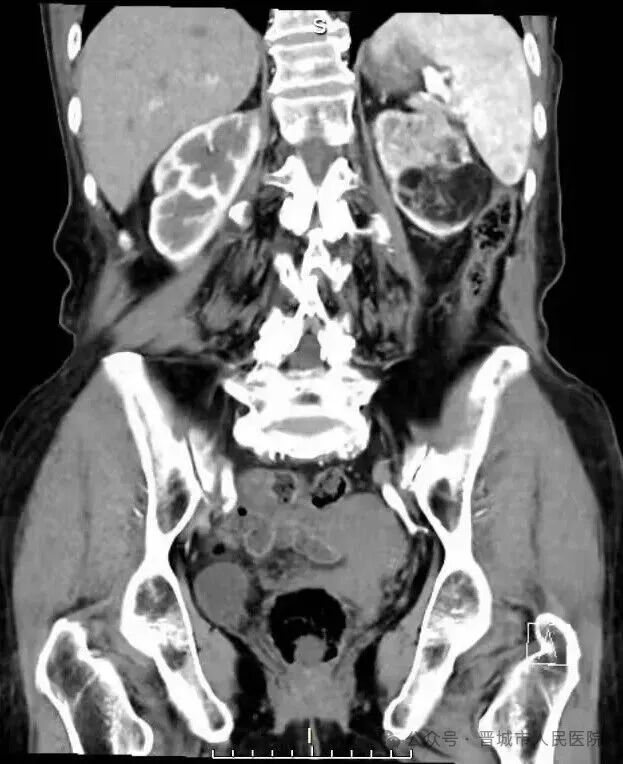

据了解,患者因体检发现左肾占位20余天入院,外院检查提示左肾肿物大小约45*55*98mm,接近十公分的肿瘤体积给治疗带来了极大挑战。更为棘手的是,患者年事已高,体质薄弱且营养状况欠佳,腹壁肌肉薄弱导致手术戳卡固定困难,传统腹腔镜手术操作空间受限、难度极高,而患者及家属保肾意愿十分强烈。